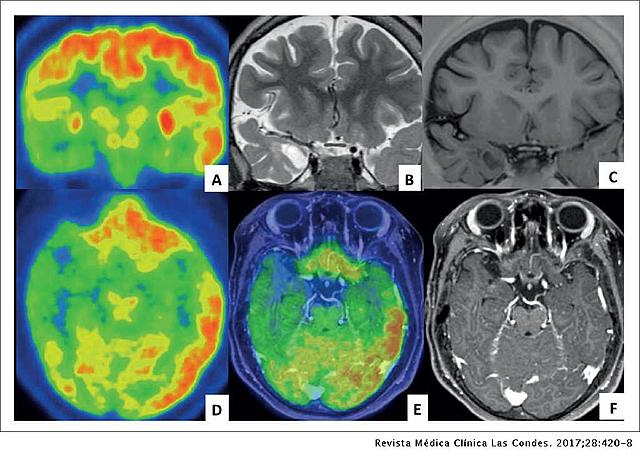

• Equipos Tecnologicos

Equipos Tecnologicos

En la evolución de la ciencia se han creado equipos los cuales pueden evidenciar infinidad de lesiones y/o enfermedades que se tienen sin necesidad de realizar cirugías, se conocen como técnicas no invasivas.

Algunas tecnicas:

Resonancia magnética funcional

Estimulación magnética transcraneal

Electroencefalografía